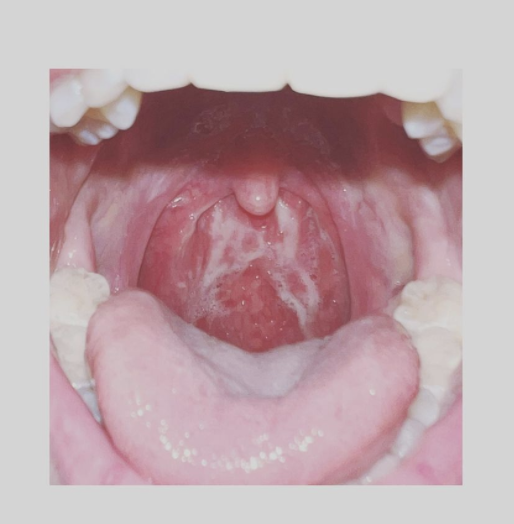

她指,其康復之路十分難捱,幾乎甚麼病徵都有,嘔吐、肚瀉、頭痛、骨痛、乾咳、痰咳、喉嚨潰瘍、發燒、發冷、呼吸不順、鼻水,而當中最令Mag痛苦的是喉嚨潰瘍,她指「我痛到每一秒都喺精神崩潰嘅邊緣,痛到完全瞓唔到,每吞一啖食物或水都要打自己大脾」。

Mag又分享其創喉嚨潰瘍的治療方法予大家參考。她指,頭2日服食有麻痺成份的喉糖、布洛芬Ibuprofen(1日3粒/400mg一粒) ,又有用噴喉痛露噴劑,以助減輕痛楚。

但去到第三天,Mag病況變得嚴重,以上的藥物「變到完全無用,喉嚨痛到升天」,她再食安痛易Arcoxia(當時我食一日一粒120mg),「令我冇咁崩潰,雖然仲係好痛,但恢復返理智。」之後Mag又有用生理鹽水、暖綠茶漱口、含生蒜片,每2小時做一次,「感覺真係再舒緩咗啲!」。她指,她先用生理鹽水洗鼻、再用生理鹽水漱口、之後用暖綠茶漱口、最後再含生蒜片,「含得幾耐得幾耐,再咬碎吞咗佢」。